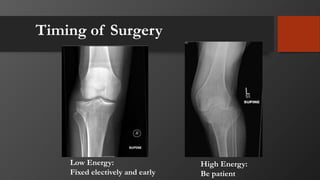

Timing of Surgery

Low Energy:

Fixed electively and early

High Energy:

Be patient